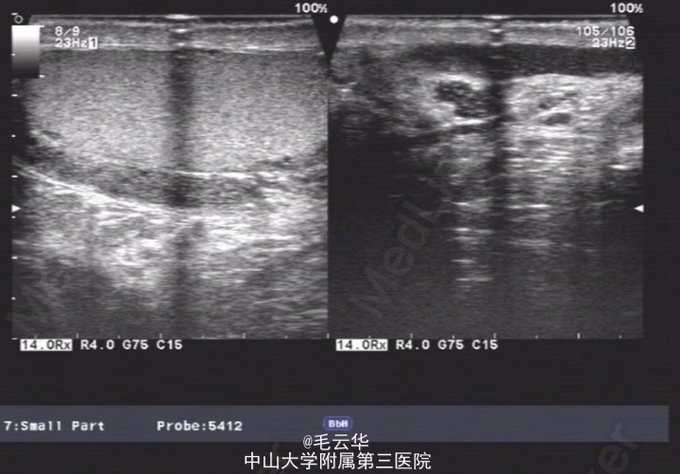

双肾区无红肿、隆起,无叩痛,双侧肋脊点、肋腰点无压痛。腹平软,双侧上中输尿管点无压痛,膀胱区无压痛。双侧腹股沟区未触及肿物,尿道外口未见异常,阴囊无水肿,双睾丸可触及,肛周皮肤无红肿。盆腔MR提示:双侧精囊腺体积缩小(未见片)。彩超提示:右侧输精管、精囊缺如可能;双侧睾丸偏大,附睾小管扩张;前列腺囊肿。精液常规提示精液量少,离心后无精子。

入院诊断:无精症查因。 入院完善术前相关检查,射精管切开+输精管探查术。麻醉成功后,取截石位,常规消毒铺巾,连接好4.5/6.5F输尿管硬镜和监视系统。经尿道进镜入膀胱,见双侧输尿管开口裂隙状,膀胱内未见异常。尿道未见明显异常,精阜稍隆起。镜下未找到双侧射精管开口,硬膜外导管引导进镜入前列腺小囊,见囊腔狭小,囊壁炎性增厚,囊内未见射精管开口,考虑射精管口梗阻,遂换用电切镜,切除部分精阜,切开双侧射精管口,再用硬膜外导管引导输尿管硬镜入射精管,进入困难,结合病史及影像学检查,提示射精管发育不良并梗阻。作双侧阴囊切口,逐层切开,游离出睾丸和精索,探查双侧输精管,见左侧输精管呈纤维条索状,未见管腔结构,右侧未见输精管,考虑为先天缺如,遂行双侧睾丸活检,术野予以止血,逐层缝合切口,术毕。手术过程顺利,麻醉效果满意,术中无出血,术后安返病房。